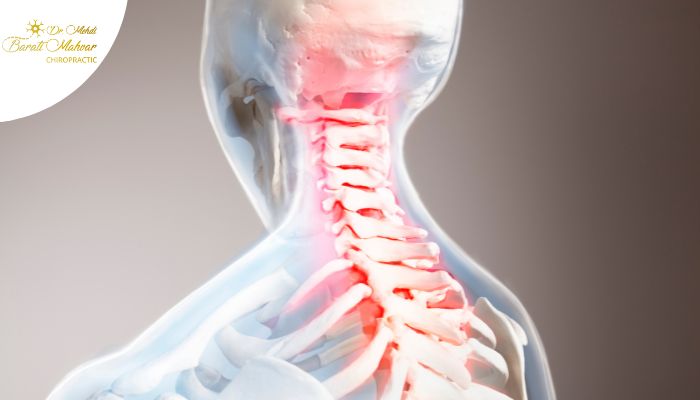

گردن یکی از حساسترین نواحی بدن است که نقش حیاتی در حرکت و حفظ تعادل بدن دارد. این ناحیه از هفت مهره گردنی تشکیل شده که بین آنها دیسکهای نرم و انعطافپذیر قرار دارند. این دیسکها فشارهای وارد شده بر گردن را کاهش میدهند. با این حال، به دلیل ساختار پیچیده گردن، هر حرکت ناگهانی میتواند موجب وارد آمدن فشار به عضلات، رباطها و حتی دیسکها شود. این آسیبها میتوانند باعث درد و اختلالات حرکتی شوند. اگر بهموقع درمان نشوند، ممکن است به مشکلات مزمنتری مانند دیسک گردن یا فتق دیسک منجر شوند.

عضلات گردن برای حرکت نرم و دقیق سر طراحی شدهاند. وقتی که گردن به طور ناگهانی حرکت میکند، این عضلات فشار زیادی را تحمل میکنند که میتواند منجر به کشیدگی، گرفتگی یا پارگی آنها شود. این آسیبها ممکن است حرکت گردن را محدود کرده و دامنه حرکتی آن را کاهش دهند. علاوه بر عضلات، مفاصل گردن نیز در معرض آسیب هستند. حرکت ناگهانی ممکن است به رباطها آسیب برساند و التهاب و درد ایجاد کند. از آنجا که رباطها انعطافپذیری کمتری دارند، آسیب به آنها معمولاً عوارض جدیتری مانند آرتریت گردن به همراه خواهد داشت.

دیسکهای گردن به عنوان ضربهگیر عمل کرده و به جذب فشارها و جلوگیری از برخورد مهرهها کمک میکنند. با این حال، حرکت ناگهانی گردن میتواند فشار زیادی به دیسکها وارد کرده و باعث بیرونزدگی آنها یا همان فتق دیسک شود. این مشکل معمولاً با درد شدید، بیحسی یا ضعف در نواحی مختلف بدن همراه است. در صورتی که دیسک بیرون زده به عصبهای اطراف فشار وارد کند، ممکن است بیحسی یا ضعف عضلانی در اندامها ایجاد شود. به همین دلیل، حرکت ناگهانی گردن میتواند پیامدهای جدیتری برای سلامت بدن داشته باشد.